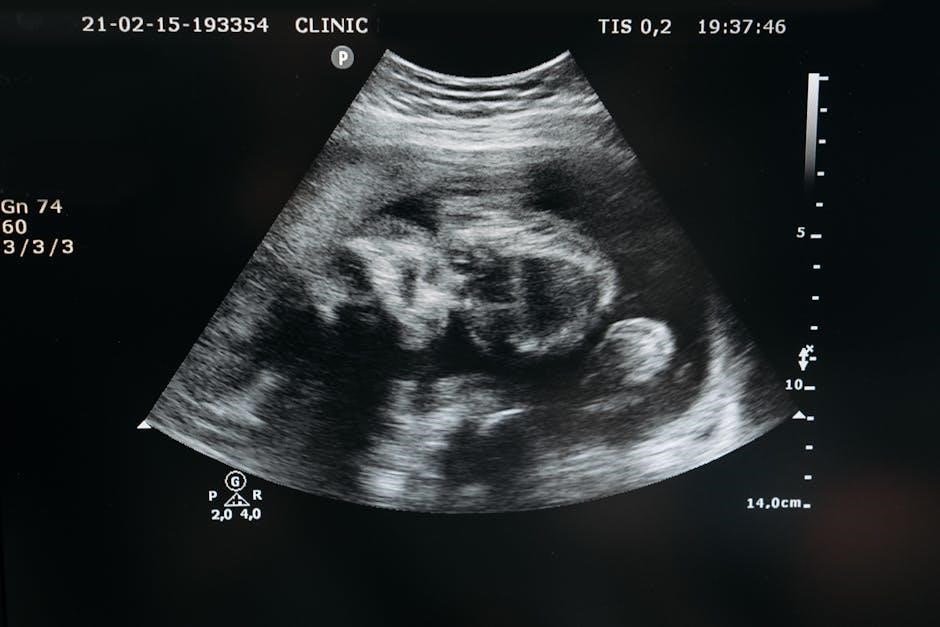

2.2. Role of Ultrasound Guidance in Liver Biopsy

Ultrasound guidance plays a crucial role in liver biopsy by providing real-time imaging to direct the needle accurately to the target tissue. It enhances precision‚ minimizing the risk of complications and improving patient safety. The ultrasound helps visualize the liver’s anatomy‚ identify the optimal biopsy site‚ and avoid major blood vessels or other sensitive structures. This technique ensures a safer and more effective procedure‚ particularly for patients with complex liver anatomy or coagulopathy. It also reduces the need for repeat procedures and improves diagnostic yield.